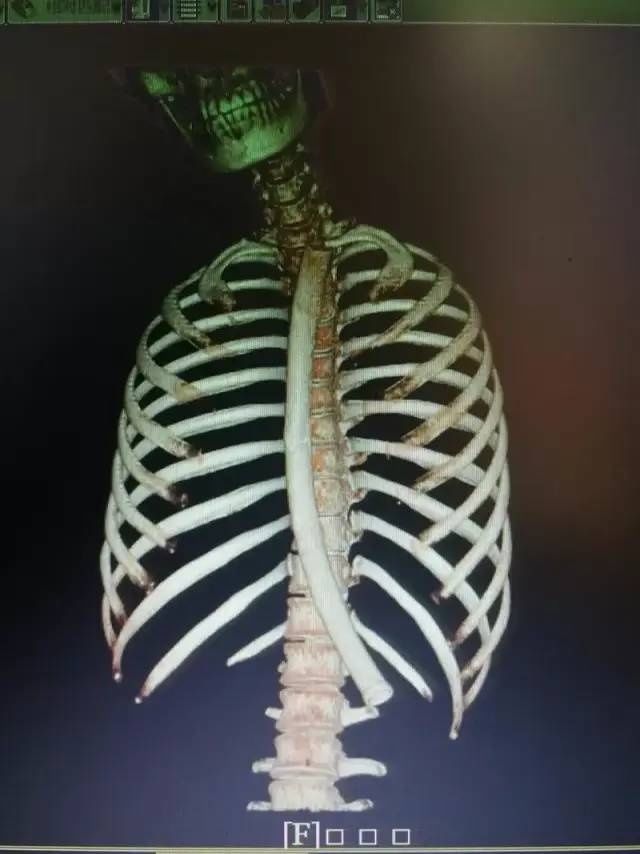

2020年5月据信息时报报道,广东的梁先生喝酒后开始大口吃鱼,一根鱼刺卡在食管,但因饮酒后神经反射的迟滞,误吞鱼刺的他浑然不知。结果刺破了食管,突破了纵膈,并插入了第六胸椎附近的主动脉里,形成了大小约4cm×5cm假性动脉瘤,随时有生命危险。经过中山大学附属第一医院心脏外科、胸外科、内镜室、影像科、B超室、麻醉科等十多个学科团队的协力合作才保住了性命,堪称九死一生。

文章图片

从患者体内取出的鱼骨,长约2.5cm